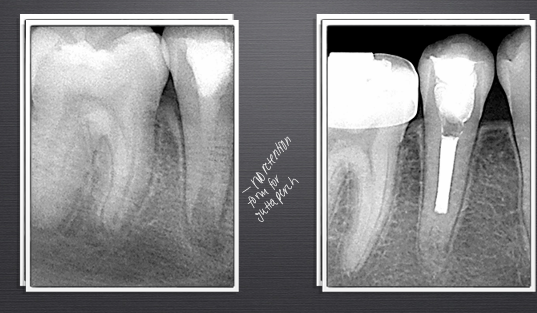

apexogenesis

-vital pulp therapy performed to encourage continued physiological root development and apical closure

-do a pulpotomy by taking out coronal pulp tissue and placing bioceramic cement on pulp stump

-takes ~24-36 hours for bioceramic cement to set- does not irritate the pulp, medically seals the pulp from contaminatory saliva

-over 6-8 months, bring patient back for recall

-calcific bridge should form from immune competent cells → rest of root able to develop

-helps to preserve ridge

apexification

-a method to induce a calcified barrier in an immature root with a necrotic pulp

-place calcium hydroxide → promotes cells in PA space to grow in from the bottom, will get barrier to form at apex

-change calcium hydroxide a couple times, will require recall